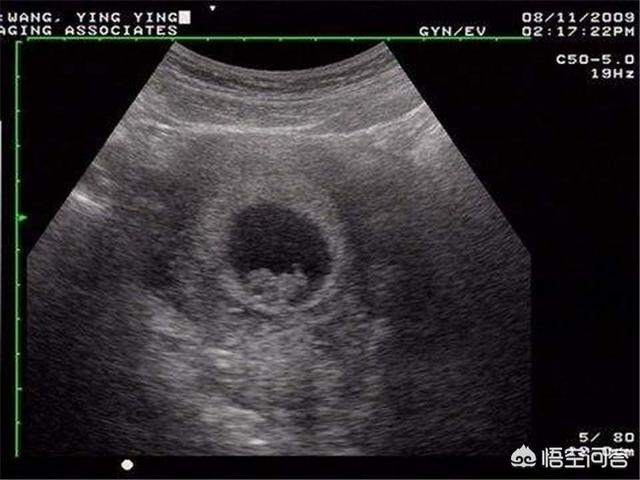

Beim B-Ultraschall werden im Allgemeinen die Entwicklung des Fötus und die Lage der Plazenta untersucht, selten geht es um fötale Erkrankungen. Nur beim 4D-Ultraschall werden fötale Fehlbildungen festgestellt, so dass es sich bei Ihrer Frage um den 4D-Ultraschall und nicht um den B-Ultraschall handeln sollte.

Mit dem Ultraschall kann überprüft werden, ob die Lage des Fötus normal ist, ob das Fruchtwasservolumen abnormal ist, ob die Nabelschnur des Fötus um den Hals gewickelt ist, ob die Entwicklung des Fötus verzögert ist und ob die Plazenta niedrig ist.

Der 4D-Ultraschall ist eine verbesserte Version des B-Scan-Ultraschalls, mit dem fetale Fehlbildungen, fetale Gesichts- und Körperorgane, Fehlbildungen der Gliedmaßen, wie z. B.: fetale Lippenspalte, Syndaktylie, vierfache Herzkammern, viszerale Ektopie,... erkannt werden können.

Die Ultraschalluntersuchung während der Schwangerschaft kann vor allem das Wachstum und die Entwicklung des Fötus, seine physiologische Aktivität, die Menge des Fruchtwassers und den Zustand der Plazenta feststellen.

Ein 4D-Ultraschall während der Schwangerschaft kann den Fötus auf angeborene Herzfehler, Hydrocephalus, Lippen- und Gaumenspalten und die Entwicklung der Gliedmaßen untersuchen. Der 4D-Ultraschall kann auch das bewegte Bild des Fötus im Körper der Mutter zeigen.

Der Ultraschall (4D-Ultraschall) ist ein notwendiger Bestandteil des Schwangerschaftstests, der vor allem für die Untersuchung der Körperoberfläche des Fötus und verschiedener Organe auf Fehlbildungen zuständig ist. Zum Beispiel: fötales Herz, Gehirn, Niere und andere Teile der Krankheit.